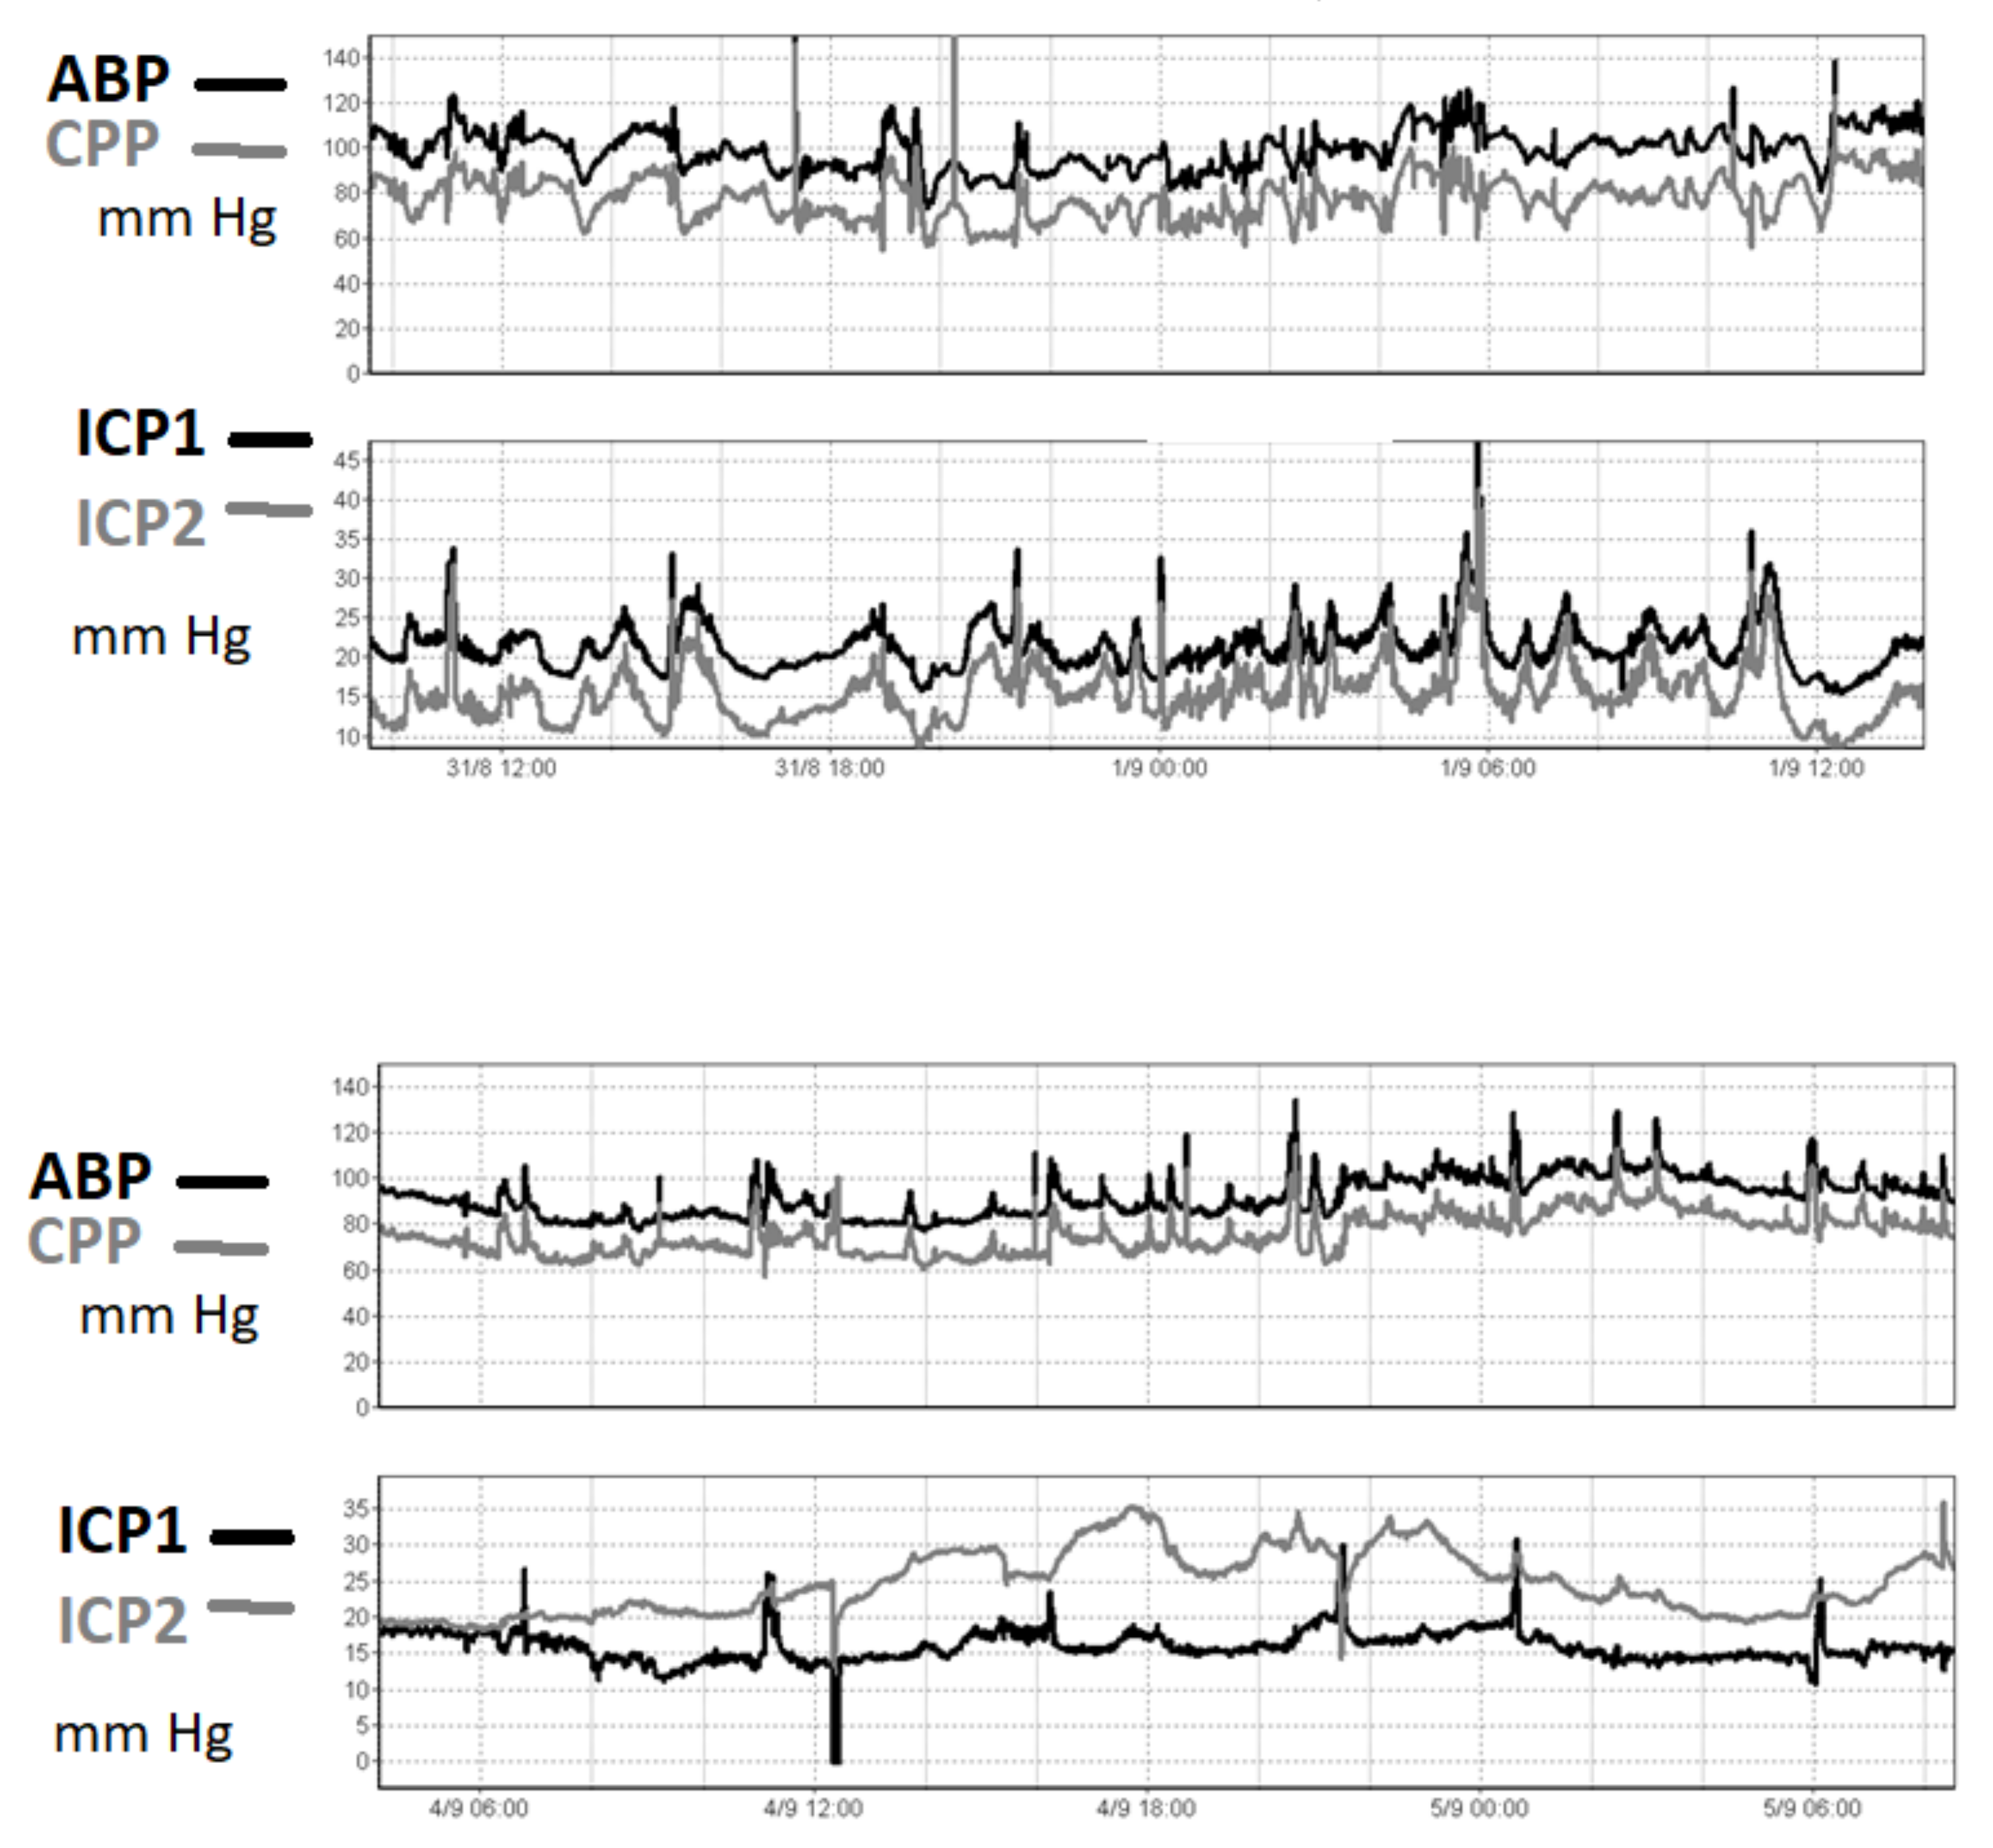

3.3. Comparing ICP Sensor Performance to Bench Testing

4.3. Agreement between Intraparenchymal Sensors and CSF Pressure in Clinical Studies